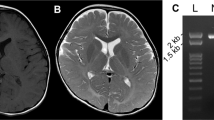

We investigated the proteolipid protein (PLP) gene in two brothers in a Japanese family with a connatal form of Pelizaeus-Merzbacher disease (PMD). Direct sequencing of the PLP gene revealed an A-to-T transition in exon 4, which led to an Asp-to-Val substitution at re-sidue 202. Their mother was confirmed to be heterozygous for the mutation. The mutation was not found in 78 X-chromosomes of normal Japanese individuals. A correlation between the clinical severity of the disease in the brothers and the Asp202-to-Val mutation in the PLP gene was suggested.